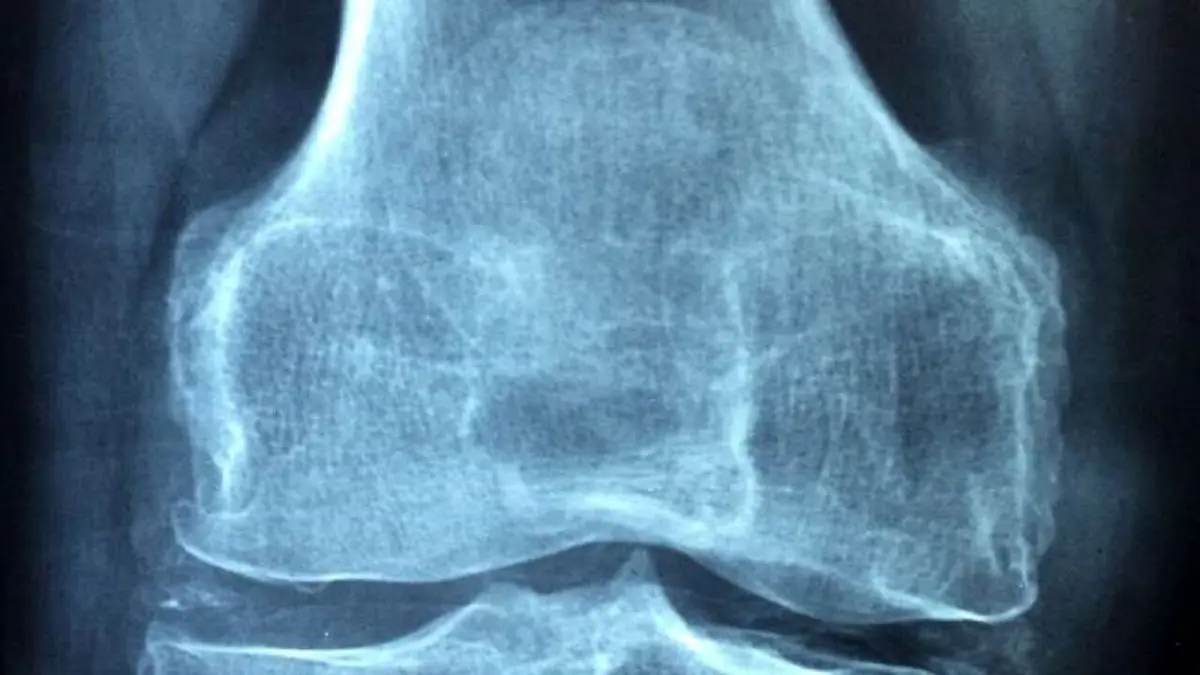

روماتیسم مفصلی زمانی رخ می‌دهد که سیستم ایمنی بدن به بافت سالم حمله کرده و آن‌ها را تجزیه می‌کند، مهمترین آن‌ها پوشش مفاصل دست، مچ، مچ پا و زانو است.

واکسن علاوه بر مهار توسعه آرتریت، کیفیت استخوان را نیز به میزان قابل توجهی بهبود می‌بخشد؛ یافته‌ای که نشان می‌دهد پس از ایمن سازی باید مزایای بلند مدتی داشته باشد.